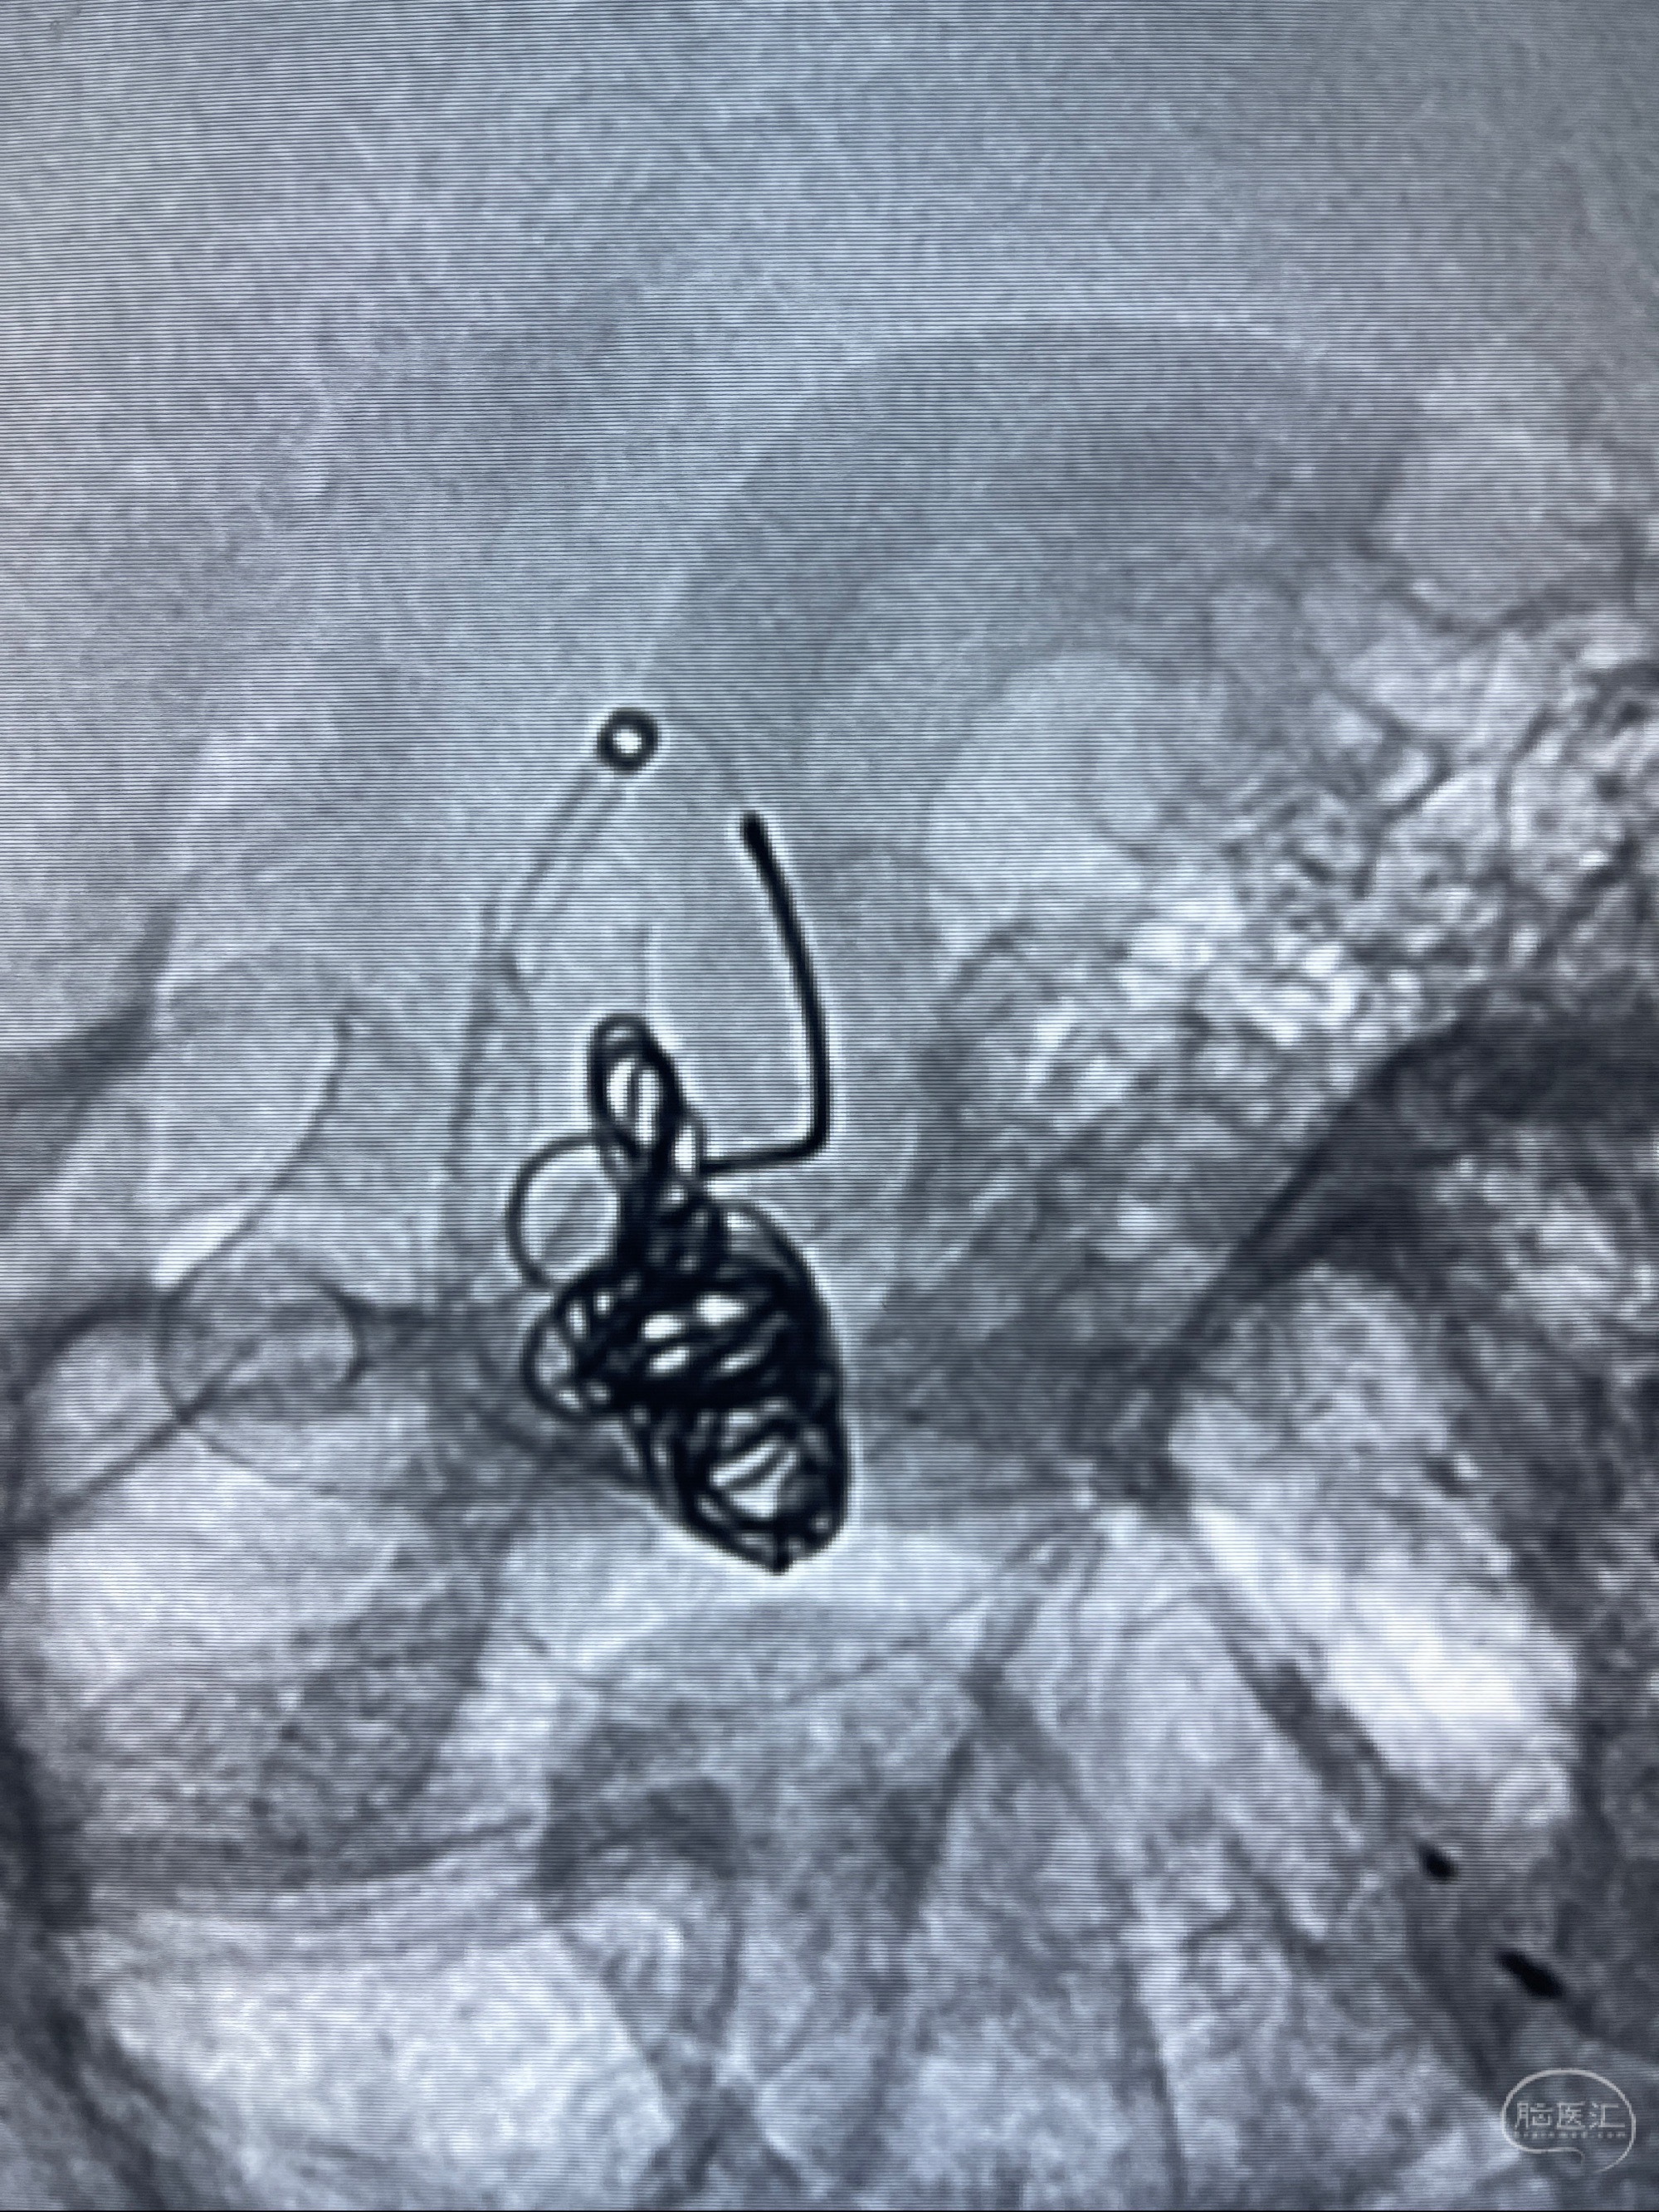

2023-07-27全脑血管造影:双侧颈内动脉眼动脉段动脉瘤,右侧较大

2023-08-01全麻下行双侧颈眼动脉瘤支架辅助栓塞

- pipeling4.5-20mm

- pipeline 4.0-20mm